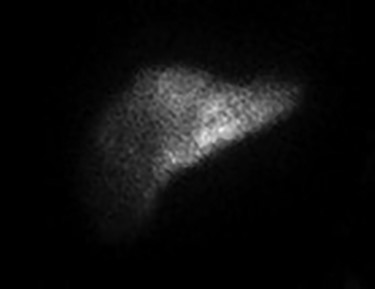

Since the placement of his HAIPC, the patient had two right-sided thoracentesis demonstrating transudate fluid (Table 1). The patient had multiple interrogations of his HAIP including a Nuclear Medicine Hepatic Pump w/SPECT/CT (Fig. 2) and an IR Venogram (Fig. 3), demonstrating adequate position and functioning of the HAIP with perfusion of the liver and no extrahepatic radiotracer. Of note, the patient’s labs pre-operatively were all within normal limits, including normal biliary labs (AST/ALT 23/15, AP 55 and T bili .3).

December 2019—IR procedure: NUC MED HEPATIC PUMP with SPECT/CT—appropriate perfusion of the liver after injection of radiotracer into the hepatic arterial infusion pump. No evidence of extrahepatic radiotracer collection identified.